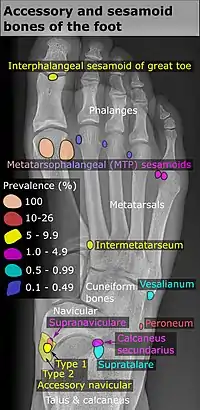

Pied

| Os | Prévalence [9] |

|---|---|

| Os sésamoïdes | |

| Sésamoïdes au niveau de l'articulation articulation métatarso-phalangienne de l'hallux | Toujours présente |

| Sésamoïde du deuxième métatarsien | 0,4% |

| Sésamoïde du troisième métatarsien | 0,2% |

| Sésamoïde du quatrième métatarsien | 0,1% |

| Sésamoïdes du cinquième métatarsien | 4,3% |

| Sésamoïde de l'articulation interphalangienne de l'hallux | 2 à 13 % |

| Os non sésamoïdes | |

| Os trigone (non visible dans la projection dorso-plantaire) | 7 à 25 % |

| Os peroneum | Jusqu'à 26% |

| Os naviculaire accessoire | 2 à 21 % |

| Os intermetatarseum | 1 à 13 % |

| Os supranaviculare | 1,0 à 3,5 % |

| Os calcanéus secondaire | 0,6 à 7 % |

| Os supratalare | 0,2 à 2,4 % |

| Os vésalianum | 0,1 à 1 % |

| Os talotibiale | 0,5% |

Un os naviculaire accessoire se développe parfois devant la cheville vers l'intérieur du pied. Cet os peut être présent chez environ 2 à 21 % de la population générale et est généralement asymptomatique[10],[11],[12]. Lorsqu’il est symptomatique, une intervention chirurgicale peut être nécessaire.

La classification Geist divise les os naviculaires accessoires en trois types[12] :

- Type 1 : os sésamoïde de 2 à 3 mmm dans le tendon distal du muscle tibial postérieur, généralement asymptomatique,

- Type 2 : osselet triangulaire ou en forme de cœur mesurant jusqu'à 12 mm, qui représente un centre d'ossification secondaire relié à la tubérosité naviculaire par un connecteur 1–2 mm de fibrocartilage ou de cartilage hyalin, des parties du tendon du muscle tibial postérieur s'insèrent parfois sur l'osselet accessoire, ce qui peut provoquer un dysfonctionnement et donc des symptômes,

- Type 3 : Un os corné présentant une tubérosité naviculaire médiale élargie, parfois symptomatique en raison de la formation d’oignons.